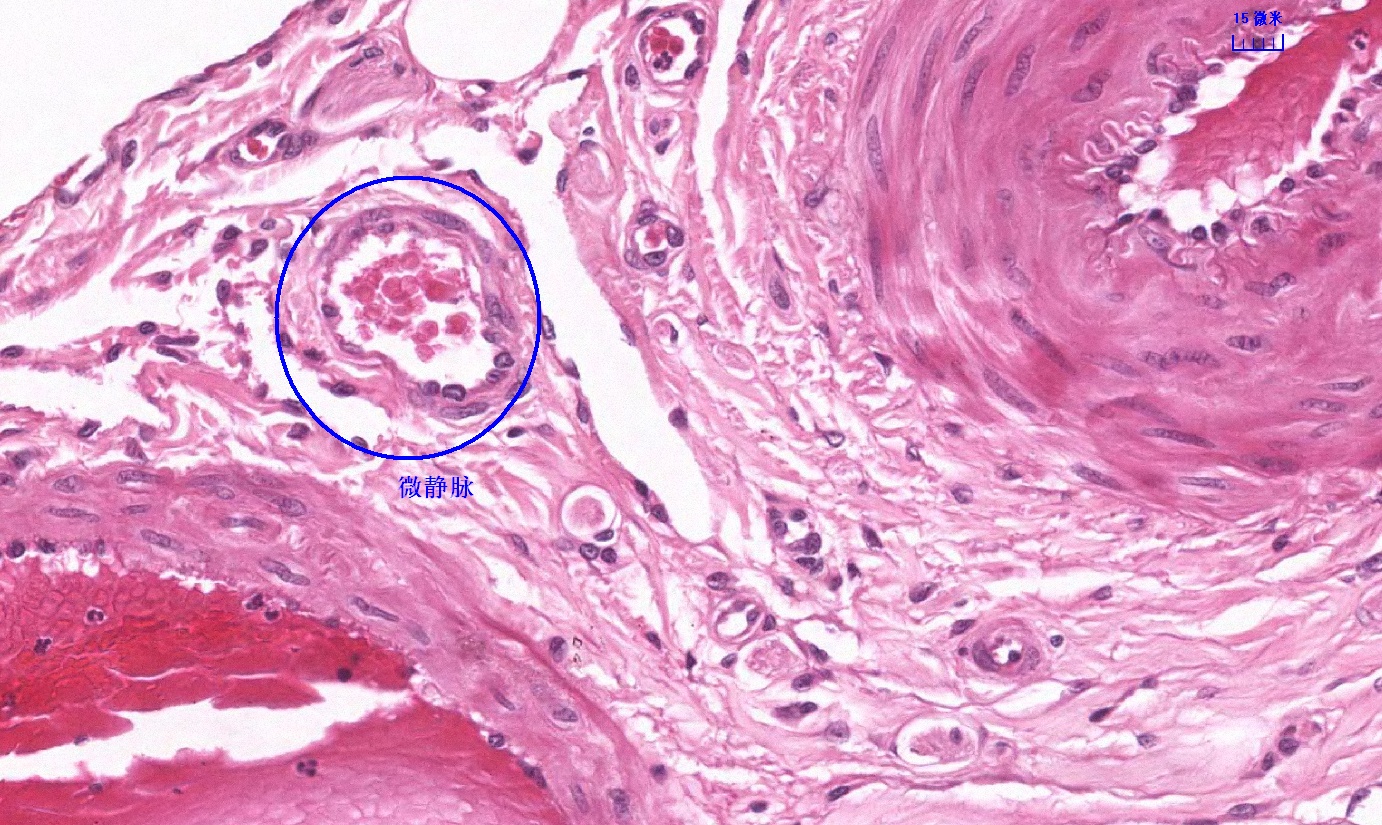

6.1 循环系统切片库

6.2 循环系统微课

6.3 循环系统课件